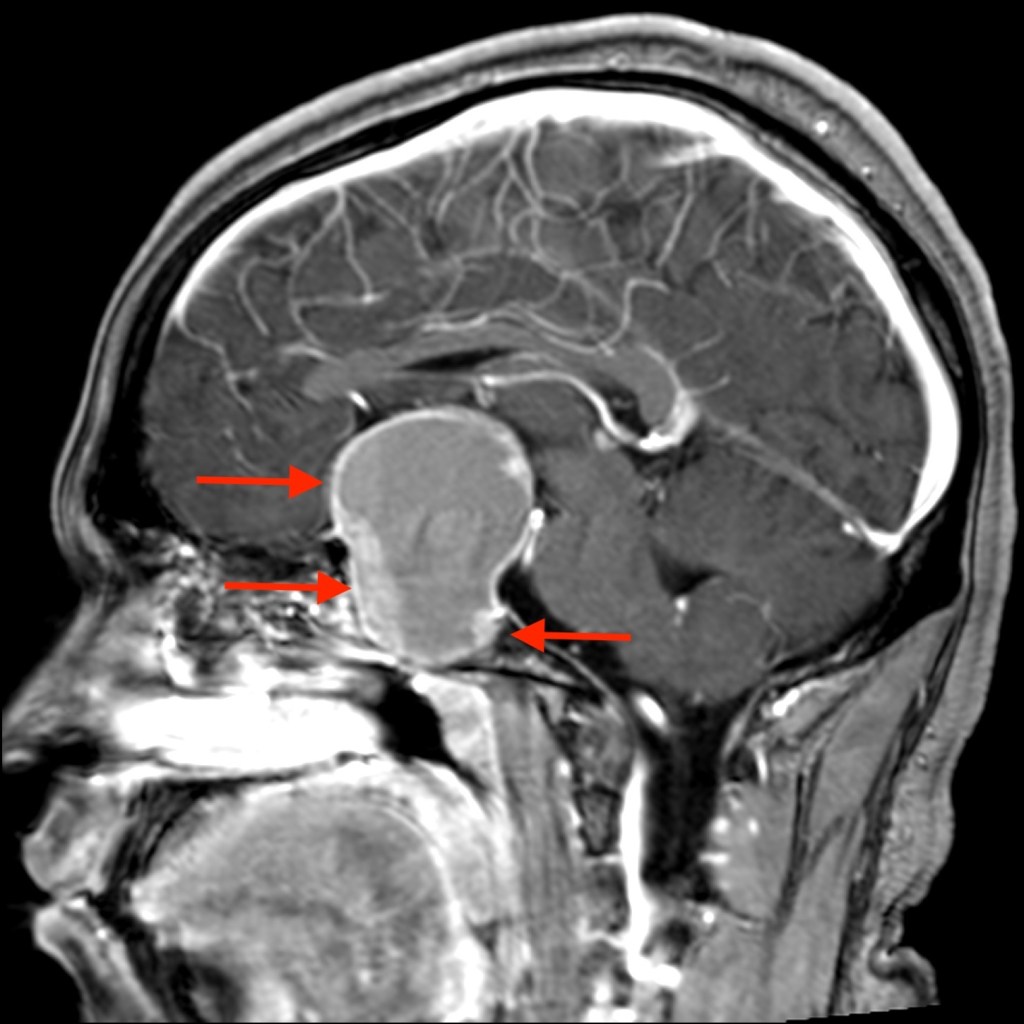

- If high PRL caused by prolactinoma, expect PRL ~100 for prolactinoma 1 cm. PRL over 500 is always due to prolactinoma

- Important distinction with respect to surgical vs medical management is whether high PRL is due to STALK EFFECT (needs surgery) vs PROLACTINOMA (needs dopamine agonist up front, even when large and with visual symptoms)